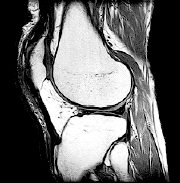

MRI. This detailed imaging test can show bone, cartilage, ligament, or muscle problems, without using X-rays.